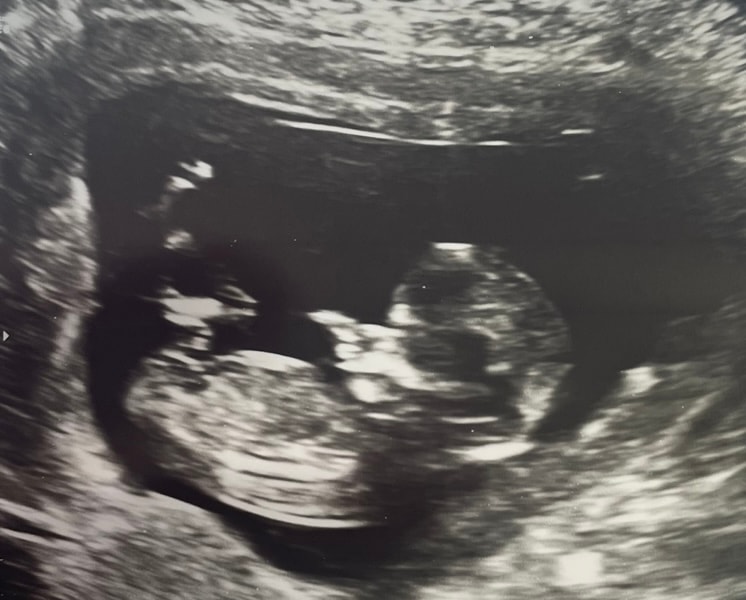

Половой бугорок в 12 недель и 6 дней. Видно?

Светлана , то что вы и обвели. На моем узи +- тоже самое было. Девочку ждём

Алина, но на 1 фото я вижу девочку 😄

Светлана , на самом первом видно.